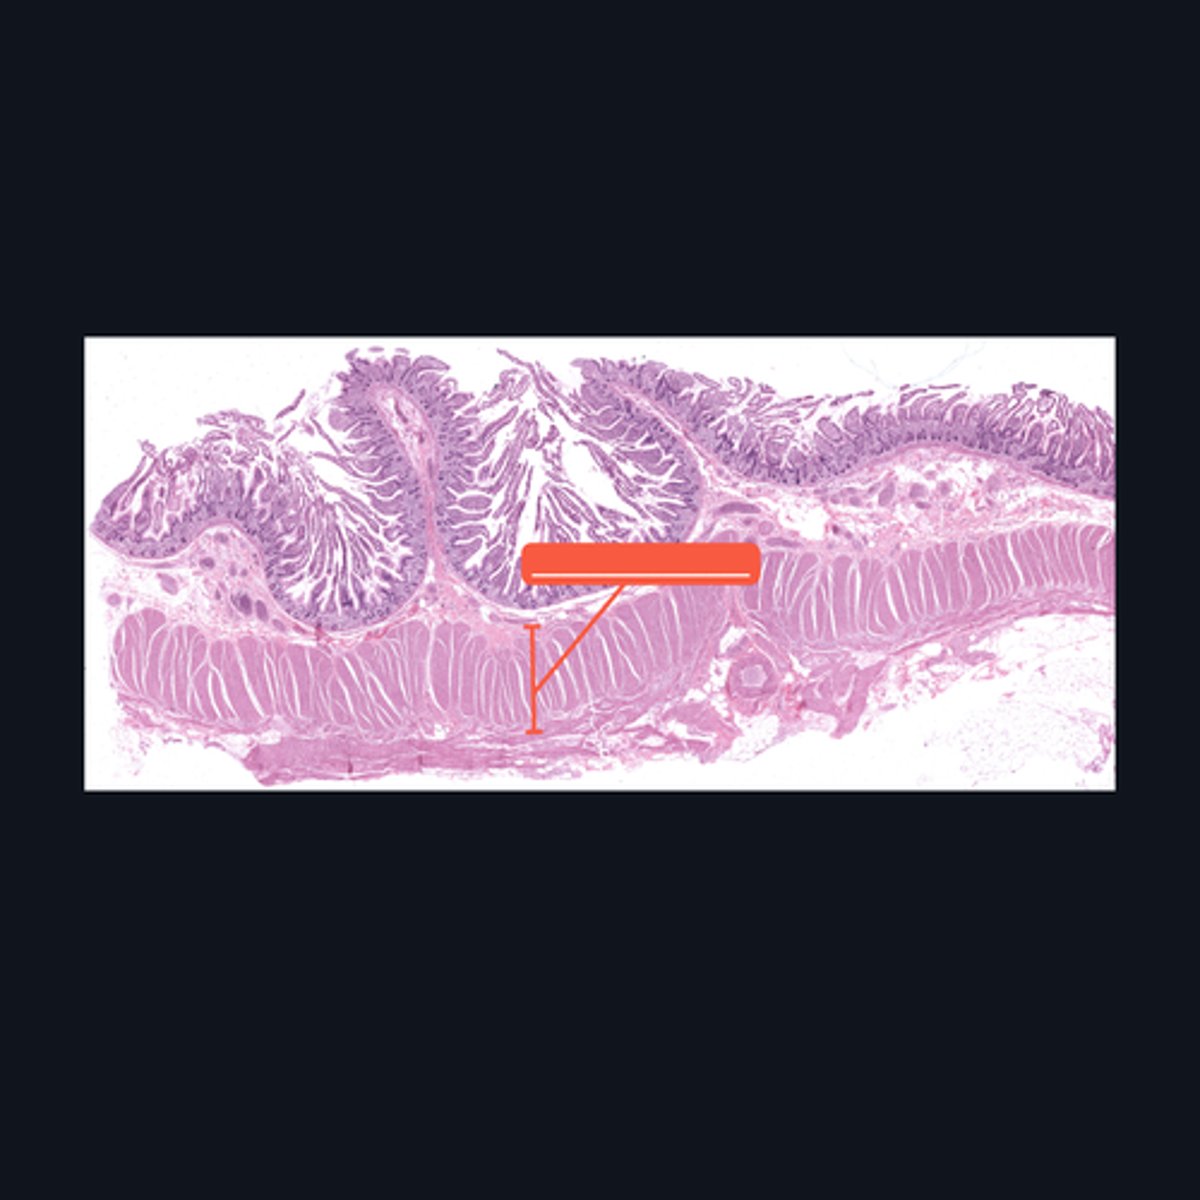

Mucosa, Submucosa, Muscularis Externa

Identify the histologic layers of the digestive tract

Submucosa

Identify the pointed histologic layer of the digestive tract